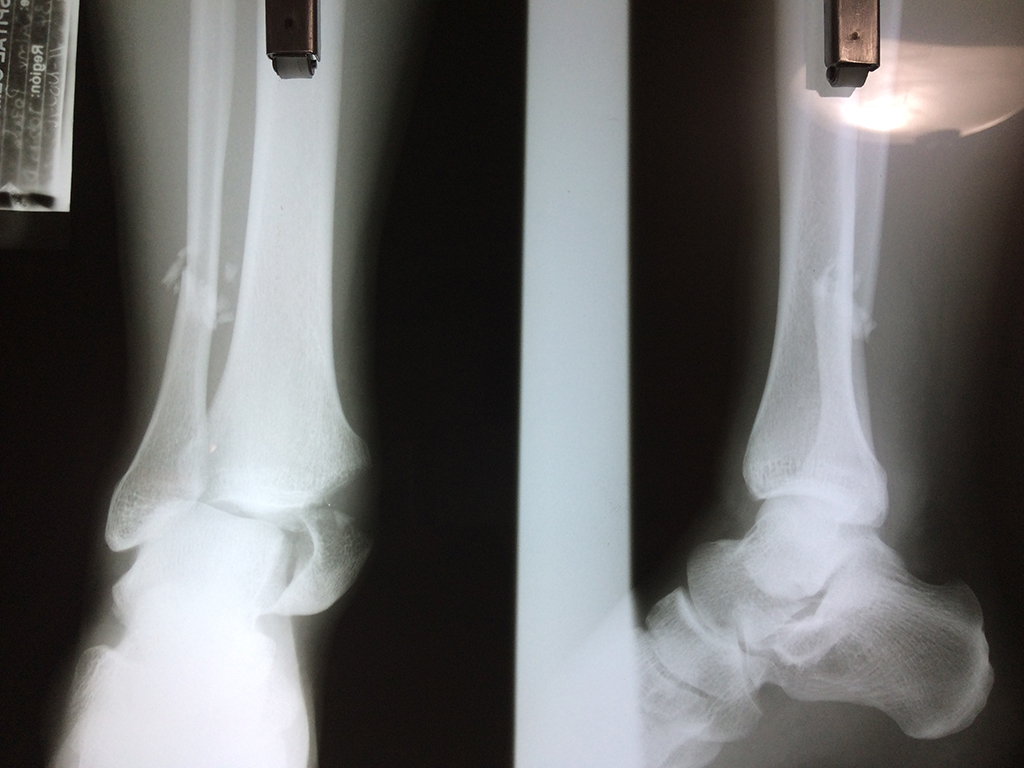

Una fractura de tobillo es la rotura de uno o más de los huesos del tobillo. Estas fracturas pueden ser:

• Parciales (el hueso está sólo parcialmente fisurado, no del todo).

Algunas fracturas de tobillo pueden requerir cirugía si:

• Los extremos de los huesos están desalineados entre sí (desplazados).